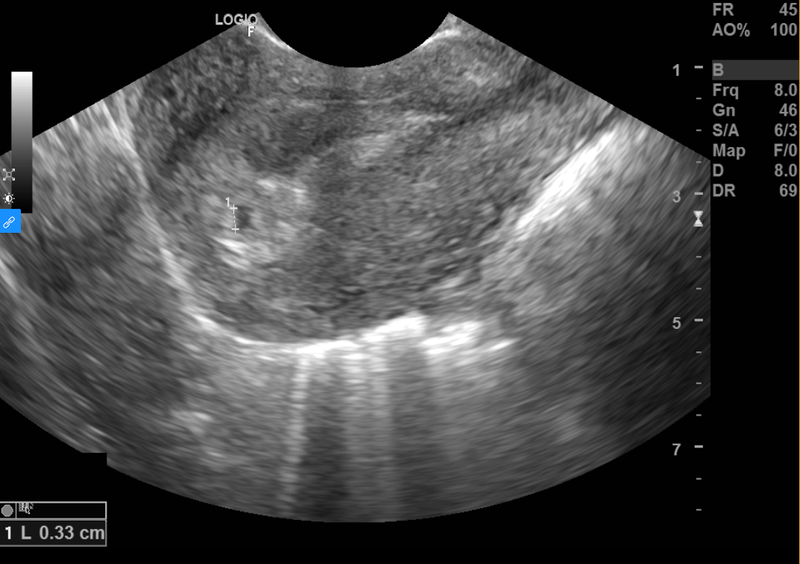

Siêu âm thai nhi từ lâu đã trở thành phương pháp an toàn và phổ biến nhất để theo dõi và kiểm tra thai nhi. Sử dụng sóng siêu âm tần số cao, kỹ thuật này ghi lại những hình ảnh của thai nhi đang phát triển trong bụng mẹ.

Siêu âm thai có thể được thực hiện qua đường bụng hay đầu dò âm đạo, cả hai đều là kỹ thuật không xâm lấn và thường kéo dài từ 15 đến 30 phút cho mỗi lần thực hiện.

Trong quá trình siêu âm, hình ảnh thai nhi sẽ hiển thị trên màn hình máy tính. Nó cho phép các bác sĩ quan sát tỉ mỉ cấu trúc và hoạt động của thai nhi, đảm bảo theo sát mọi cột mốc phát triển. Ngoài việc đánh giá sự tăng trưởng của thai nhi, siêu âm còn giúp phát hiện những bất thường tiềm ẩn, từ đó chủ động đưa ra các biện pháp nhằm đảm bảo kết quả tốt nhất có thể cho cả bé và cha mẹ.

Siêu âm được thực hiện khoảng 10 đến 13 ngày sau khi trứng thụ tinh sẽ giúp mang lại hình ảnh rõ ràng về thai nhi trong bụng mẹ. Bác sĩ sẽ xác định bất kỳ dấu hiệu bất thường nào, chẳng hạn như có mang thai ngoài tử cung hay không. Việc kiểm tra này có tác dụng ngăn ngừa các biến chứng tiềm ẩn vì thai làm tổ ngoài tử cung khi phát triển to có thể bị vỡ, gây chảy máu ồ ạt cho mẹ bầu. Nếu không được phát hiện và cấp cứu kịp thời, thai phụ có thể bị đe dọa tính mạng.